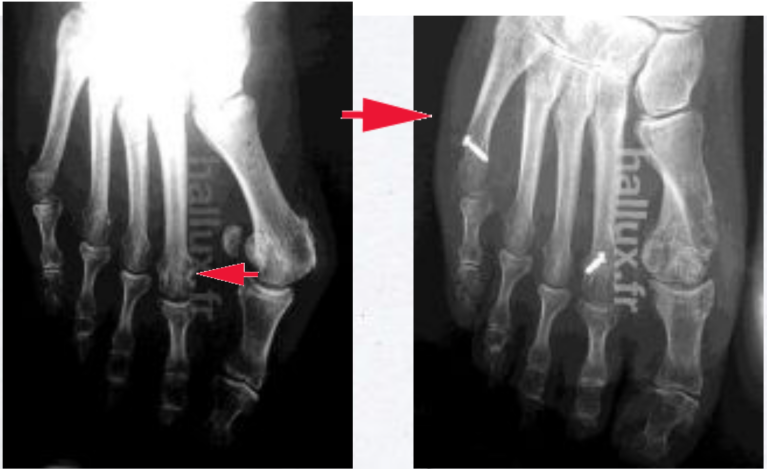

RADIOGRAPHIES

(biseau par voie mini-invasive)

Ces radiographies montrent la correction de l'hallux valgus ; la translation de la tête du premier métatarsien permet de la rapprocher de la tête du deuxième métatarsien. L'espace entre ces deux métatarsiens est réduit. L'angle inter-métatarsien est normalisé.

La forme et la taille de la tête métatarsienne restent physiologiques. La surface articulaire, contrairement à d'autres techniques où l'on rabote la tête, est intacte, sans réduction de surface. Son orientation peut être corrigée.

Enfin, on peut observer que les sésamoïdes, petits os normalement situés sous la tête du premier métatarsien, ont retrouvé leur position normale, non luxés...

L'intervention de biseau est une opération physiologique, qui s'efforce de restituer une anatomie normale avec des angles inter-métatarsien et métatarso-phalangien normaux, sans altération ni diminution de la surface articulaire.